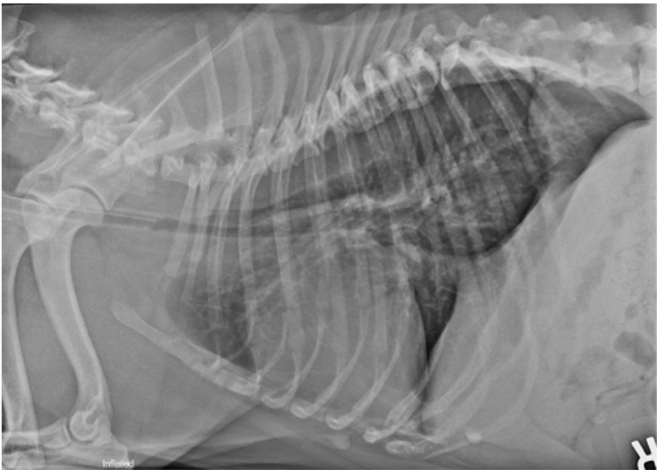

• what has happened in this image?

tracheal hypoplasia / stenosis

You can also survey inflated radiographs of the thorax, perform a neurological examination as well as routine haematology and blood biochemistries